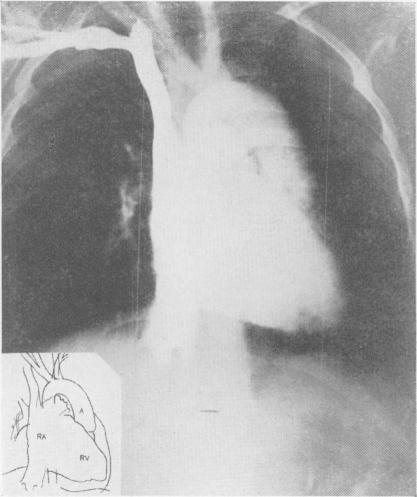

Angiocardiographic demonstration of pulmonary stenosis.

Acta Radiol (Stockh). 1953 Dec;40(6):547-53. doi: 10.3109/00016925309177063.